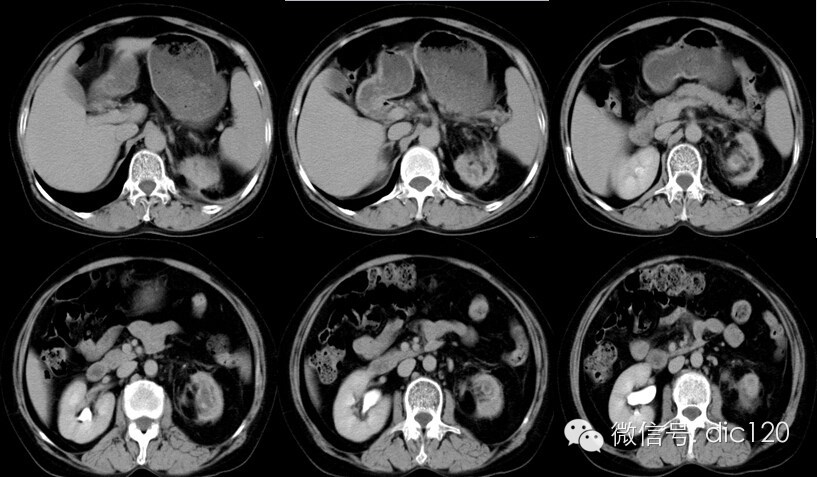

影像表现:CT平扫左肾体积变小,肾皮质变薄,肾盂扩张、壁增厚,见小点状高密度影,肾盏扩张,增强扫描病变周围组织呈环形强化,囊变区不强化,肾周模糊,筋膜增厚,临近腹膜增厚,左侧输尿管近段见结节状高密度结石影。 分析:1、中年妇女,左上腹不适;2、肾盂肾盏扩张、壁增厚,增强环形强化;3、输尿管及肾盂小结石;4、肾周筋膜增厚。 符合肾脏感染性病变,考虑黄色肉芽肿型肾盂肾炎。 |